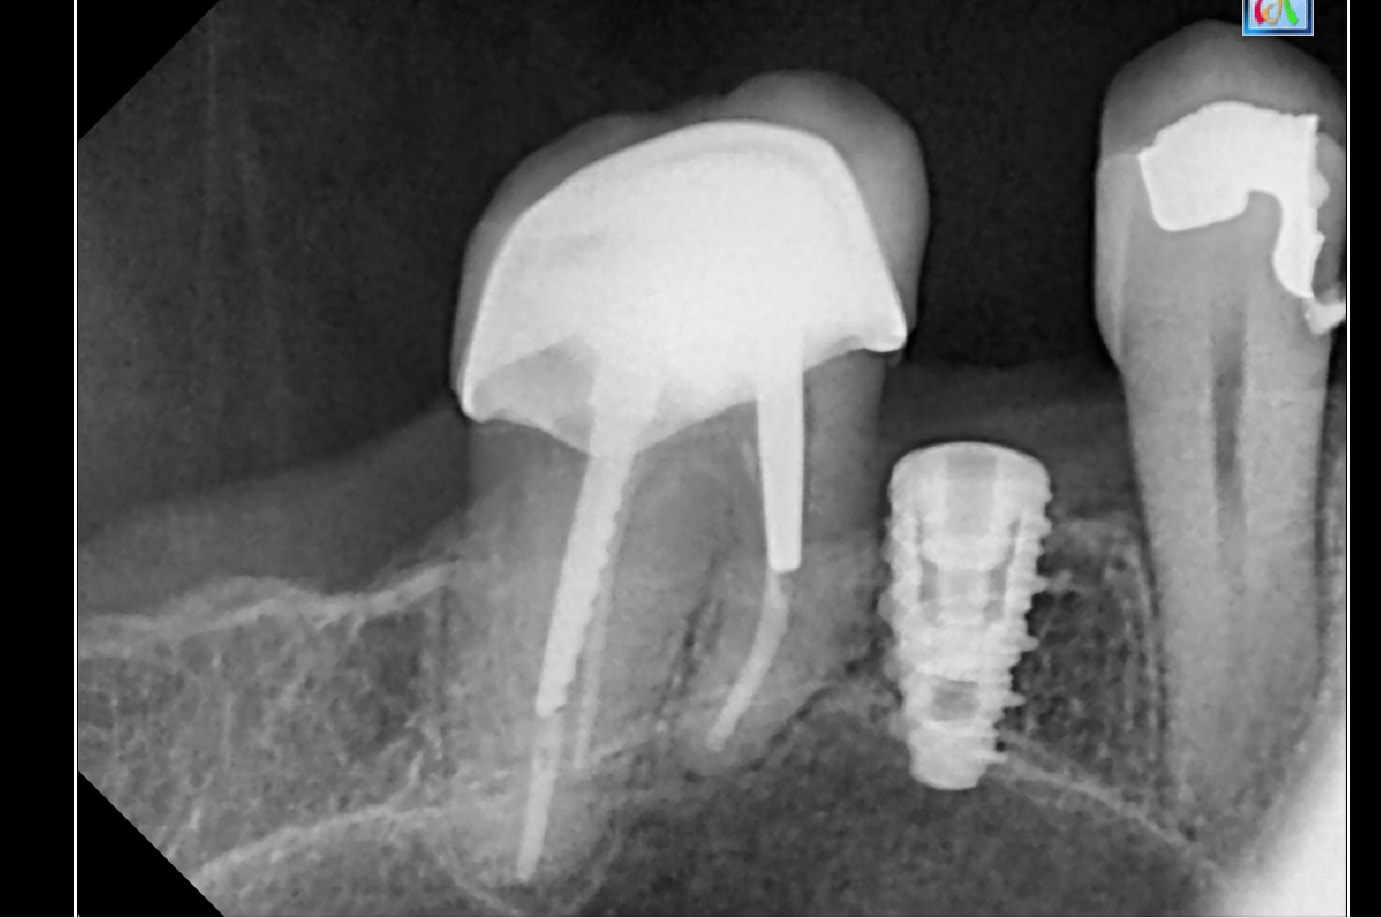

pourrais-tu me dire la marque de ces implants

Kontact de chez Biotech ….!

> Kontact de chez Biotech ….!

yes!